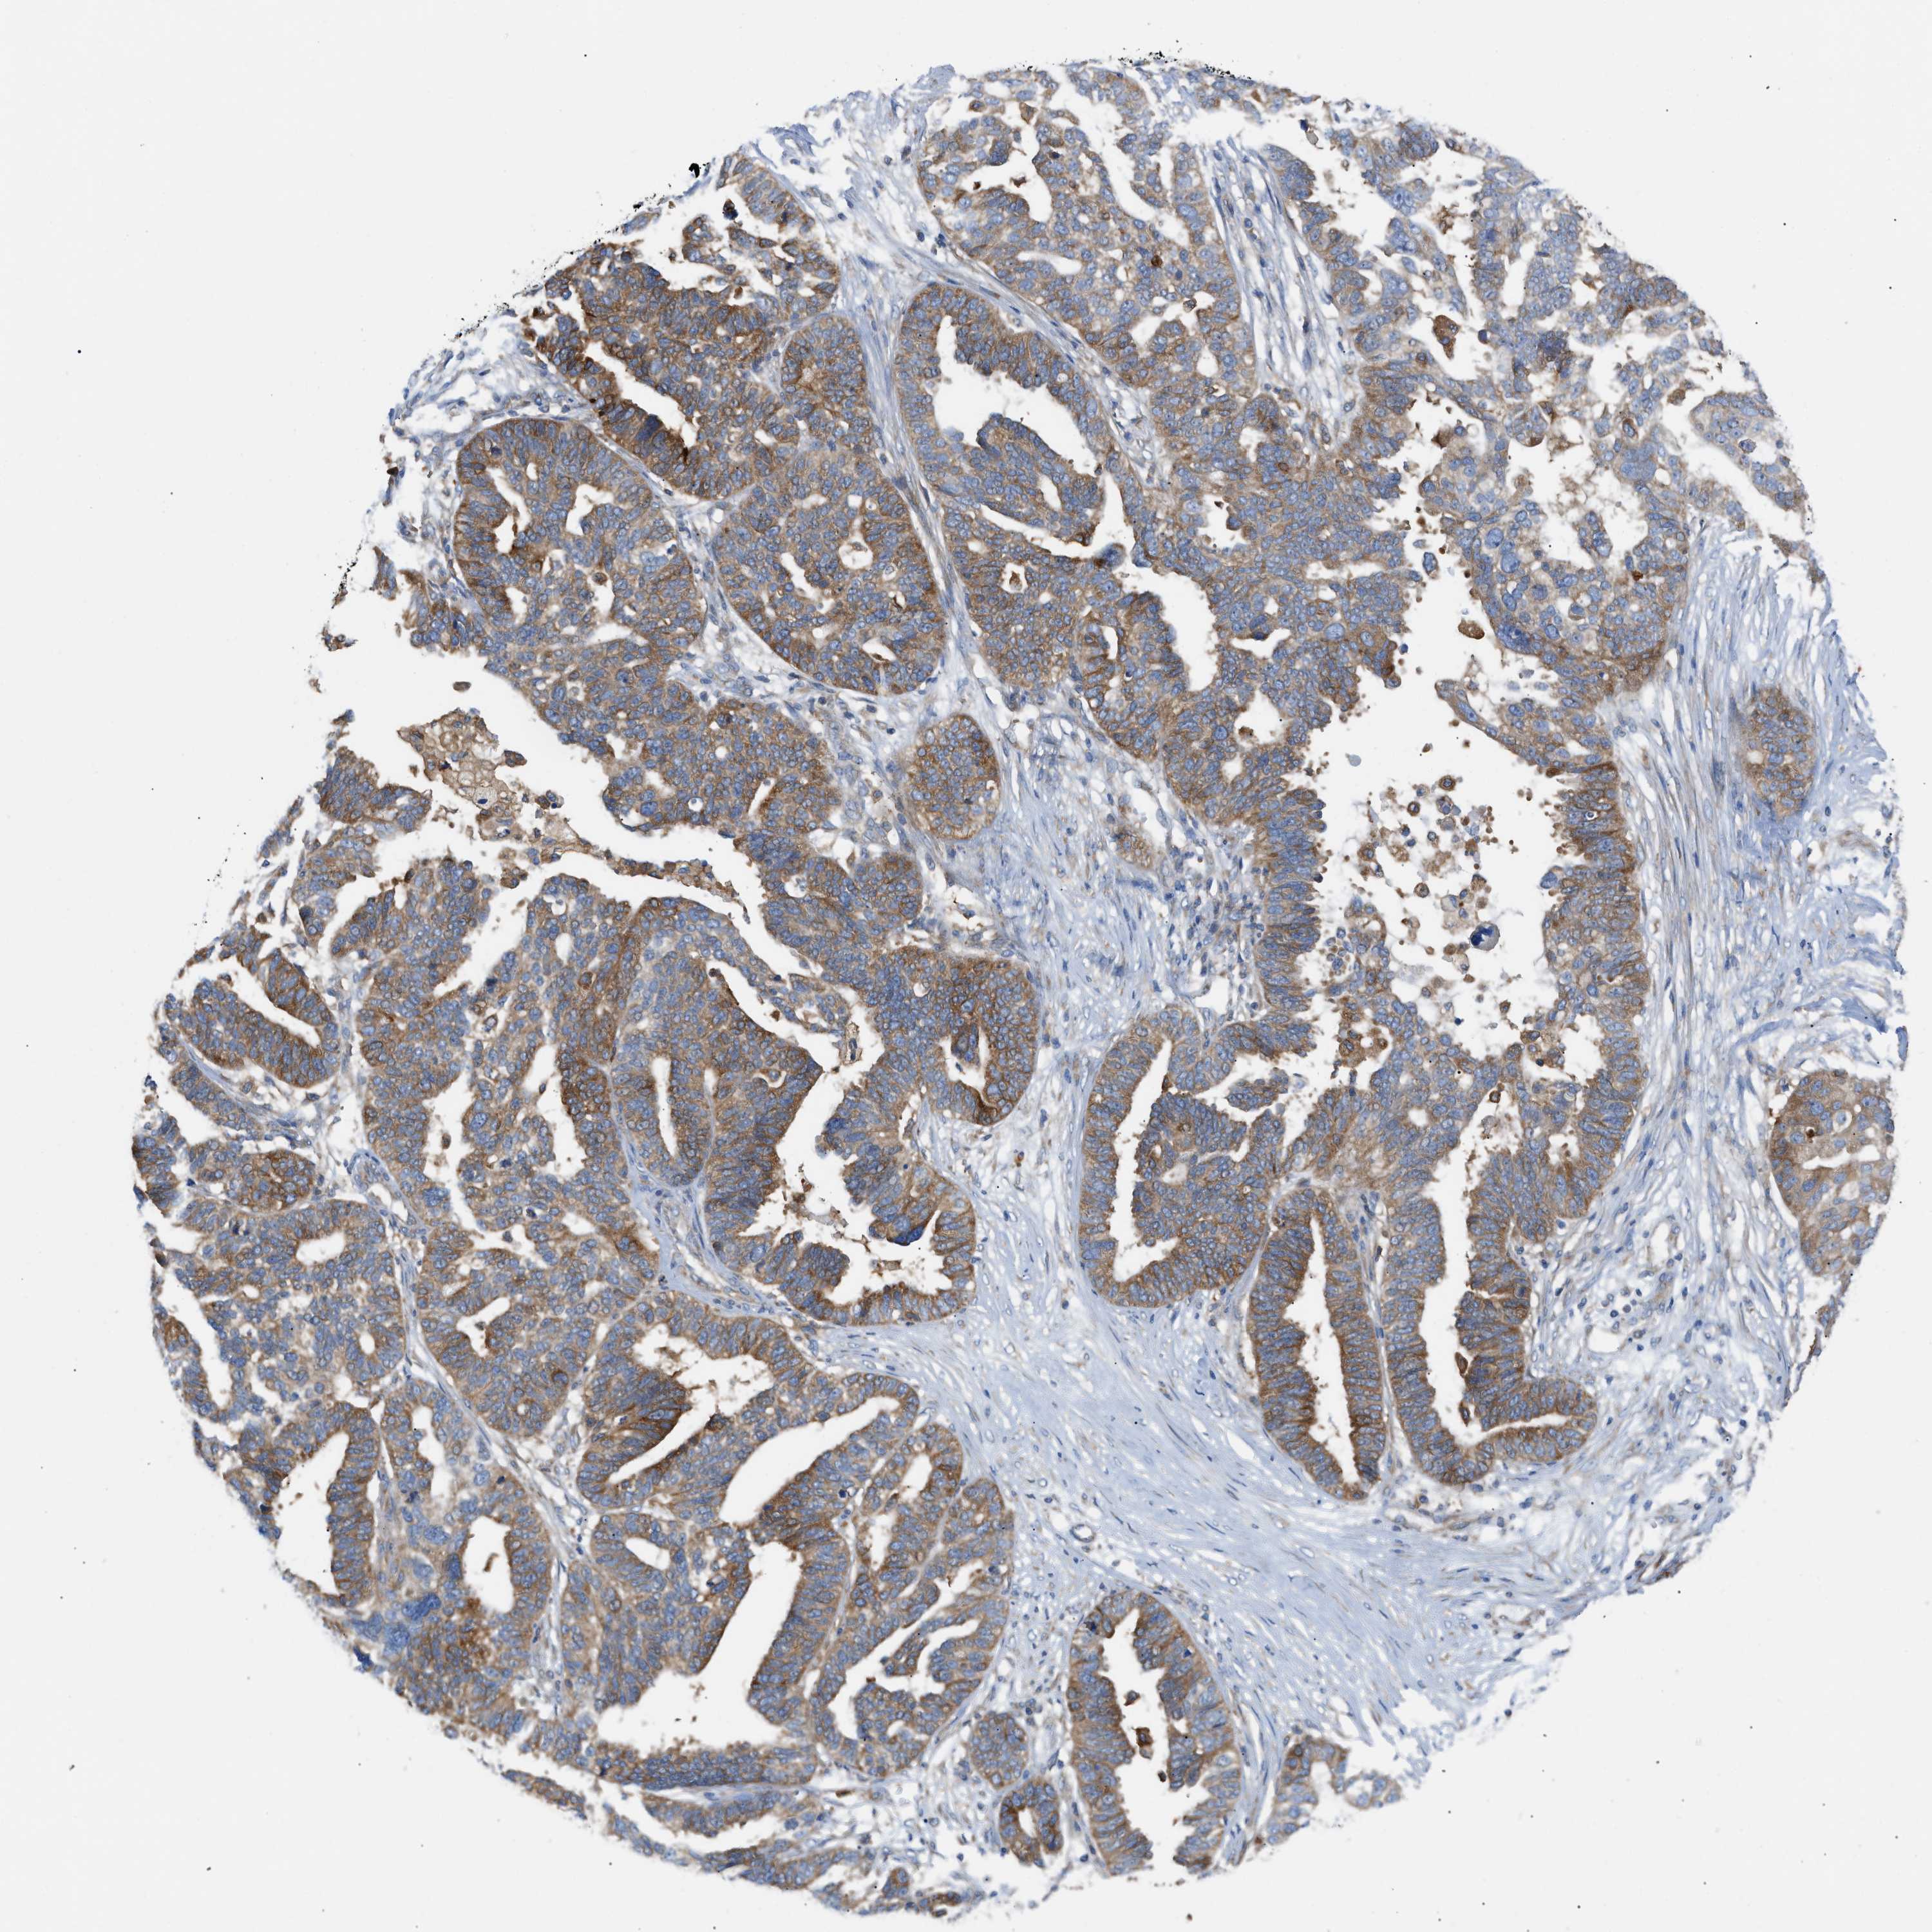

OVARIAN CANCER - Protein expressioni

A mouse-over function shows sample information and annotation data. Click on an image to view it in a full screen mode. Samples can be filtered based on level of antibody staining by selecting one or several of the following categories: high, medium, low and not detected. The assay and annotation is described here.

Note that samples used for immunohistochemistry by the Human Protein Atlas do not correspond to samples in the TCGA dataset.

Antibody stainingi

Antibody staining in the annotated cell types in the current human tissue is reported as not detected, low, medium, or high, based on conventional immunohistochemistry profiling in selected tissues. This score is based on the combination of the staining intensity and fraction of stained cells.

Each image is clickable and will lead to virtual microscopy that enables deeper exploration of all samples and also displays staining intensity scores, fraction scores and subcellular localization as well as patient and tissue information for each sample.

Antibody HPA016471

Staining

High

Medium

Low

Not detected

Intensity

Strong

Moderate

Weak

Negative

Quantity

>75%

75%-25%

<25%

None

Location

Nuclear

Cytoplasmic/membranous

Cytoplasmic/membranous,nuclear

Cystadenocarcinoma, serous, NOS

Carcinoma, endometroid

Cystadenocarcinoma, mucinous, NOS

Carcinoma, NOS